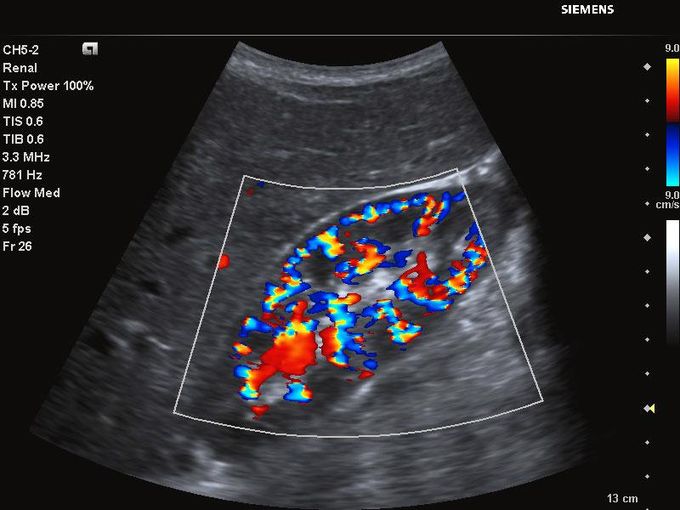

Кроме новой техники, можно заказать восстановленные медицинские системы: ультразвуковые сканеры, томографы, флюороскопы, ангиографы и хирургические установки С-дуга.